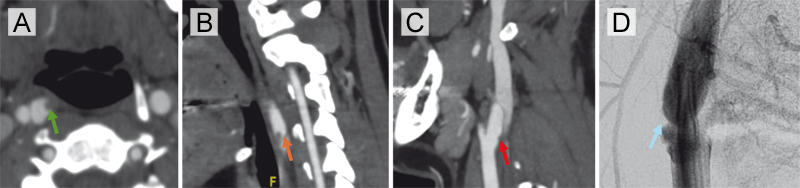

Figure 3. Interval development of thrombus over a carotid artery web in a patient with recurrent ischemic events.

(A) Axial CTA at the time of large vessel occlusion demonstrates a carotid web in the right internal carotid artery with superimposed thrombus (orange arrow). (B) Corresponding sagittal view confirms the presence of thrombus overlying the web in the proximal right internal carotid artery (green arrow). (C) Imaging performed three weeks earlier during workup for TIA shows the same carotid web without thrombus (red arrow).